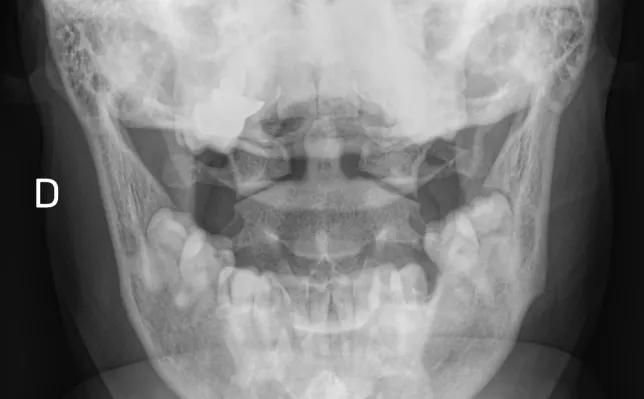

Los casos clínicos ilustran los conceptos desarrollados en los artículos a través de ejemplos reales.

Cada caso propone un análisis sistemático de las imágenes, integrando los hallazgos radiológicos con el contexto clínico y el razonamiento diagnóstico.